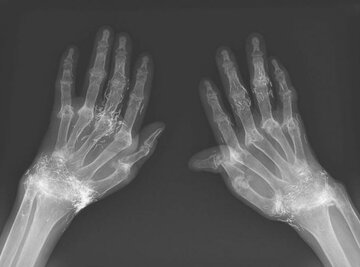

نادیا زکالوند: در یک مورد نادر پزشکی در کره جنوبی، پزشکان هنگام درمان درد و خشکی شدید زانوهای زنی که به آرتروز مبتلا بود، متوجه وجود صدها رشته طلای خالص در بافت‌های اطراف زانوهای او و البته دست‌هایش شدند.

اما این روش هم نه‌تنها دردی از این زن دوا نکرد، بلکه زانودرد او را هم شدت بخشید. درنهایت او مجبور شد دوباره به بیمارستان مراجعه کند و پزشکان هنگام تصویربرداری از زانوها و دست‌های او متوجه صدها رشته ریز و نازک از طلا در بافت‌های اطراف زانو و دست‌های این زن شدند.